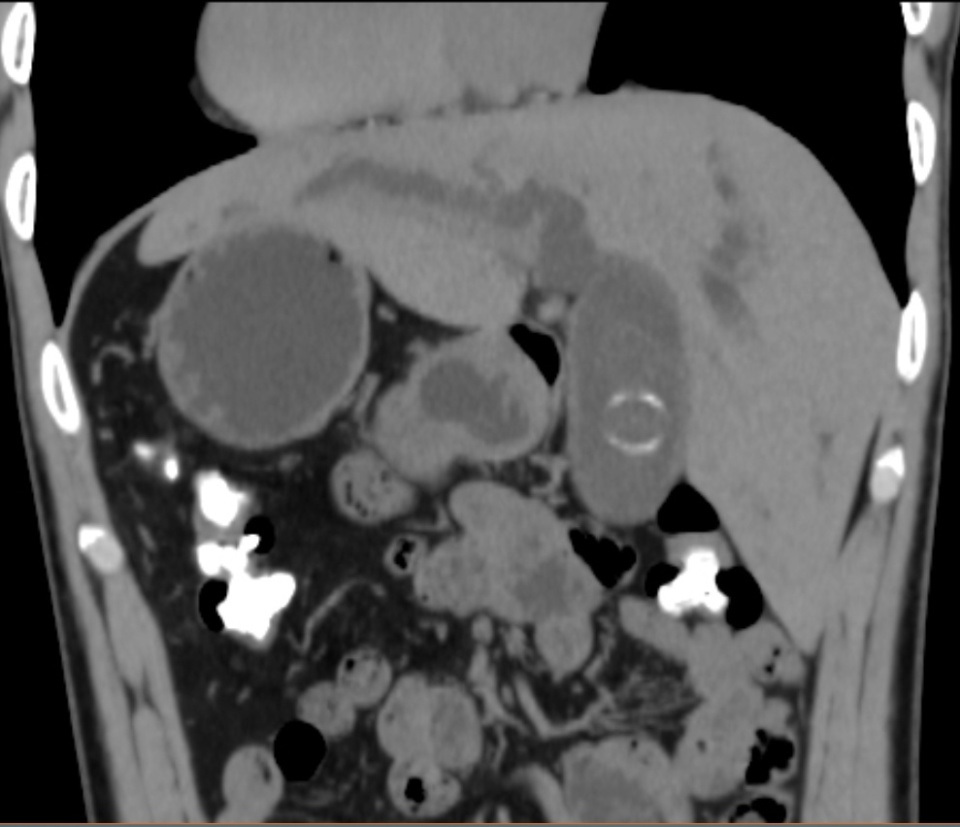

图片

反转的脏器CT影像